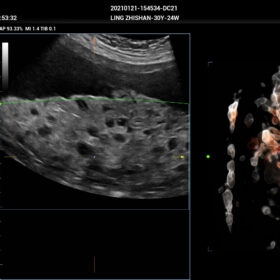

- Smart FLC 2D/3D – Automatic Follicle Counting and measurements in 2D/3D mode